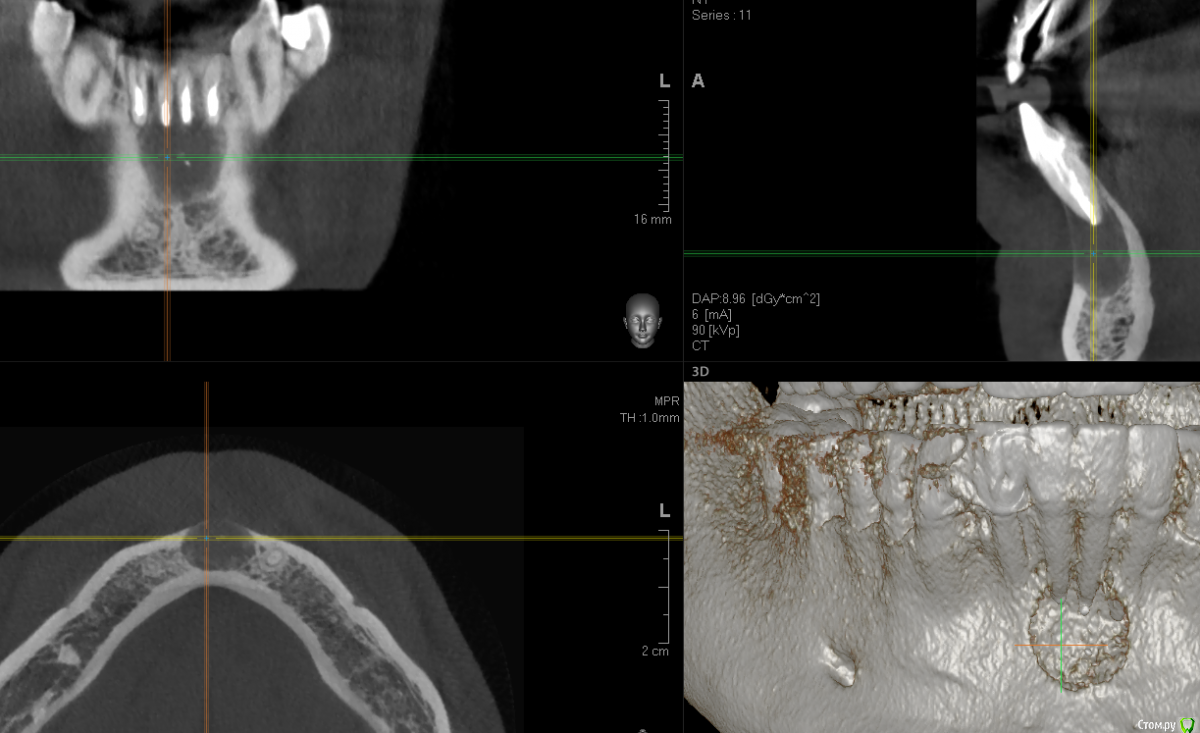

dirkdigglerdirk Опубликовано 24 августа, 2017 Поделиться Опубликовано 24 августа, 2017 Здравствуйте, уважаемые стоматологи. Пожалуйста, прокомментируйте мою ситуацию. Киста впервые обнаружена около 4 лет назад, появилась боль при накусывании, открывались гнойные свищи в области центральных резцов. Были пролечены каналы с закладкой лекарства калосепт, в результате достигнута положительная динамика (уменьшение кисты). Затем через 4 года киста вновь воспалилась - на данный момент ситуация такая как на снимках (снимки свежие). Зубы на данный момент не болят, последний раз свищ открывался около 4 месяцев назад. Зубы под коронками - три под временными (поставили недавно, с перспективой замены на постоянные после операции и наблюдения), один под постоянной коронкой со вкладкой. Каналы в трех зубах перелечены в июне с закладкой лекарства калосепт. Врачом запланирована операция цистэктомия с резекцией верхушек корней 4 зубов, возможно с ретроградной пломбировкой каналов и с закладкой костных гранул в полость. Скажите, каковы варианты лечения? Каковы перспективы сохранить эти зубы? Как бы действовали вы? Интересно ваше мнение, спасибо. Если требуется, могу выложить КТ полностью. Ссылка на комментарий